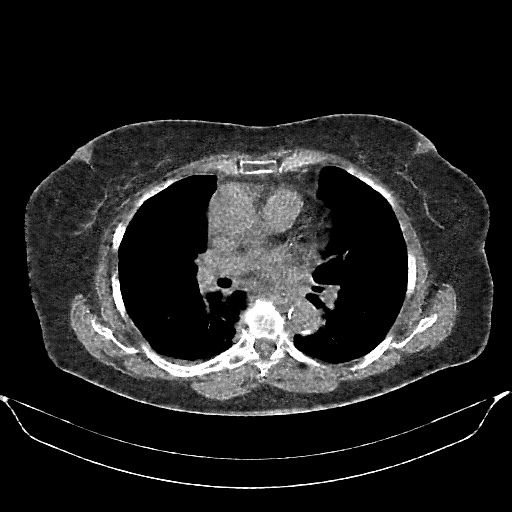

Original VENOUS CT scan

No window - Raw intensity values

Lung window (WL -600, WW 1500 β†’ Low βˆ’1350, High +150)

Mediastinum window (WL 40, WW 400 β†’ Low βˆ’160, High +240)